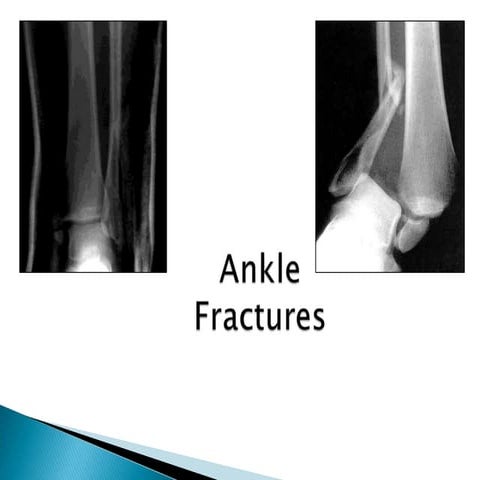

Investigations

• Plain X ray

• USG

• CT scan

• MRI